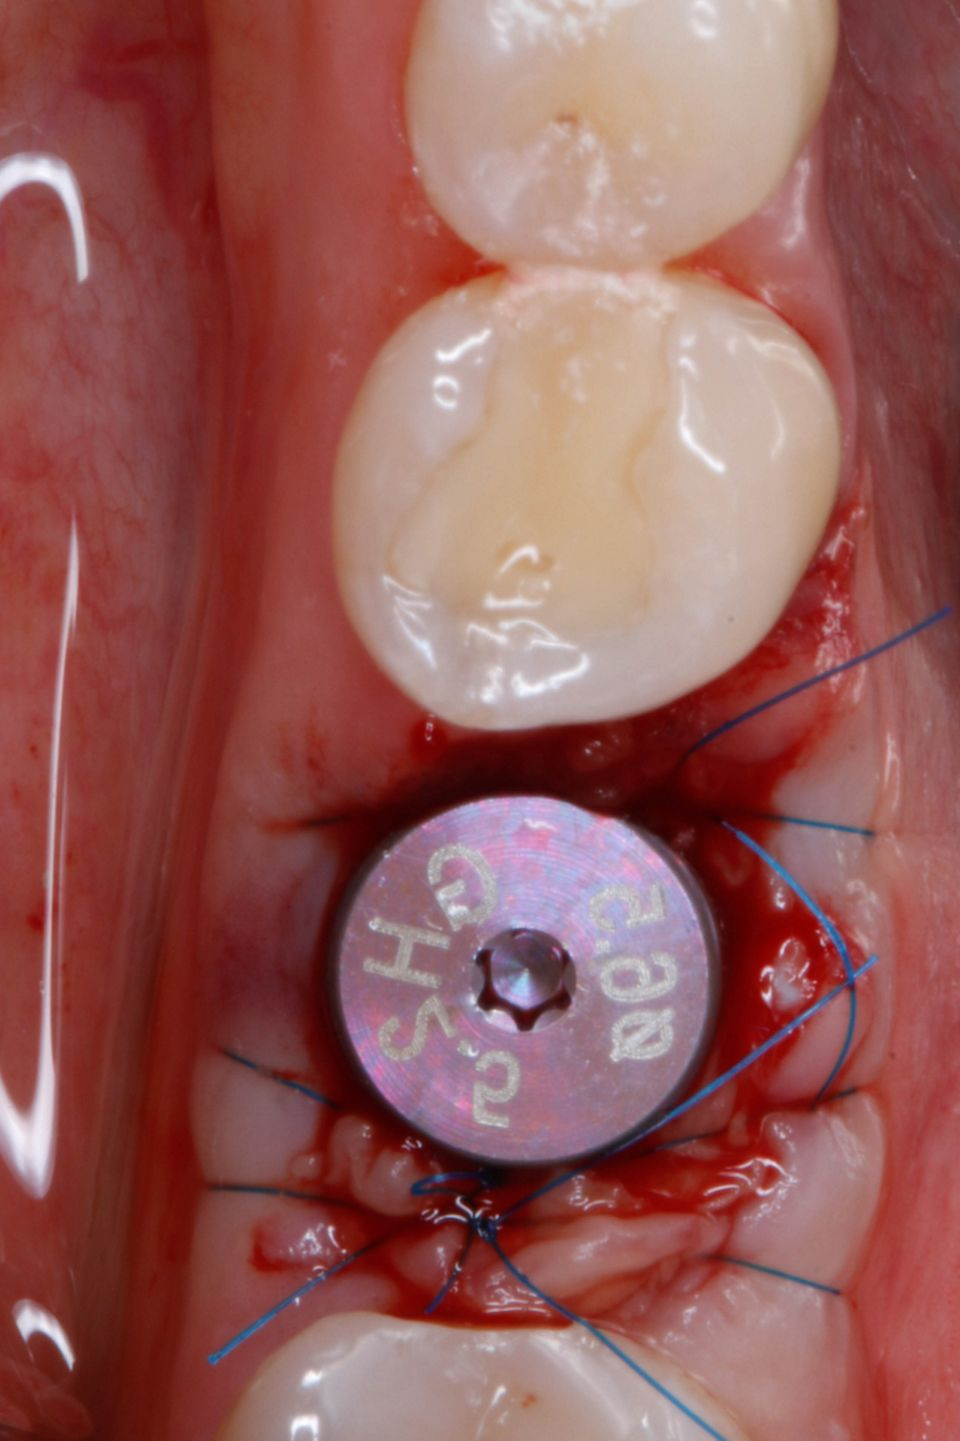

#36 牙的手术过程从局部麻醉和下牙槽神经阻滞开始。通过分割磨牙根实现无翻瓣反射的无创拔牙;从而保留肺泡壁和根间隔膜(图3-4)。仔细清洁牙槽,形成种植体路径并放置Straumann ® BLX 种植体 5.5 x 8 mm (图 5-7)。为了促进非浸没式愈合,将标准愈合基台连接至种植体。骨壁和种植体之间的间隙填充有同种异体骨材料颗粒(maxgraft®,botiss 生物材料,德国)。应用富含血小板的纤维蛋白(PRF)来实现适当的初步愈合。调整软组织边缘并用聚丙烯 6/0 缝合,使愈合基台暴露(图 8-9)。将粘性牙周Reso-Pac ®敷料(来自德国杜伊斯堡的Hager & Werken)放置在治疗区域上以协助愈合过程(图10)。

图6